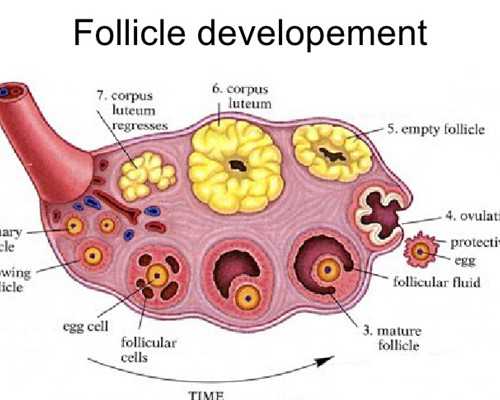

如果要談到試管嬰兒的話,可能很多人都認為這是一個比較專業的話題,其實大多數的人會發現,我們在各個不同的時間段做試管嬰兒這項手術的時候,他們也會需要各種不同的胚胎。當然在無錫人民醫院試管嬰兒手術進行過程當中,可能很多人問到的問題最多的,也就是這個關于試管嬰兒的手術情況,大家不妨一起來了解一下,我們也可以對所有的胚胎等級進行全面劃分和了解。

一級胚胎和二級胚胎

從無錫人民醫院的胚胎情況來看,一級胚胎的細胞數或者是發育的天數基本上都是合適的,那么通常情況下有7個細胞到9個細胞到9個細胞細胞的大小全部都是均勻的,而且碎片通常都是小于5%,這種情況下整個胚胎也就會有所差別,二級胚胎的細胞數和發育的天數基本上是合適的,有6個細胞到10個細胞細胞的大小全部都可以忽略不計,碎片在5%~20%之間。

三級胚胎和4級胚胎

我們在選擇做試管嬰兒手術的時候,你會發現三級胚胎和四級胚胎也是有所不同的,三級胚胎的細胞數和發育的天數明顯呈現著不符合的狀態,細胞的大小明顯不均勻,碎片在21%~50%左右,如果是4級胚胎的話,細胞的數量或者是整個發育的天數也會呈現著明顯不符合,細胞的大小有著嚴重不均勻的情況,而且它們的碎片會在50%左右,所以大家在這方面一定要格外注重。

囊胚期胚胎等級如何劃分?

在人民醫院選擇做試管嬰兒這項手術的時候,在囊胚期間如果要對所有的等級進行劃分,那么這種情況下采用的全部都是人類囊胚分級系統,也就是說可以從整個囊胚的擴張程度來進行了解,有各種不同的細胞團來進行滋養,而且要在各個不同的方面進行評價,整個囊胚腔的擴張程度也分為很多不同的等級,等級越高也就越好,對于三級以上的囊胚,那么后期會有各種不同的字母,分別代表著內部的細胞團或者是滋養層的等級。